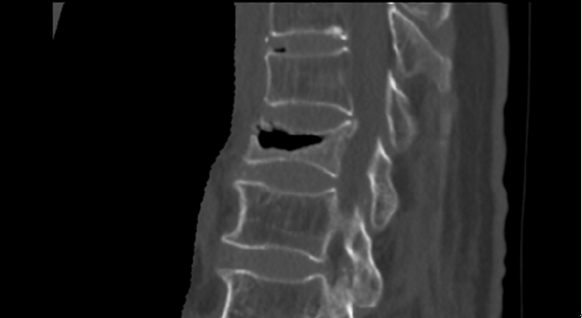

CT可见真空征

自2017年以来,谢岗院区骨外科引进一项专门针对老年骨质疏松后导致的新鲜椎体骨折手术---经皮球囊扩张椎体后凸成形术,简称PKP术。PKP手术简单易行,手术创伤小,手术时间短,术中出血仅数毫升,还没有抽血化验的量多,术中仅需要基础麻+局麻即可,无需插管全麻及腰麻,术后仅需卧床数小时即可下地行走,术后第二天即可出院,腰痛症状术后缓解率100%。这在谢岗老年腰痛的治疗上,具有划时代的意见,对广大老年腰痛患者更是极大的福音!